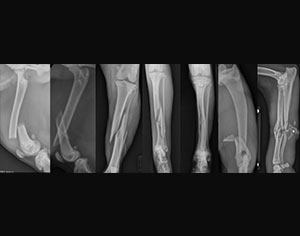

- Bone cancer (osteosarcoma)